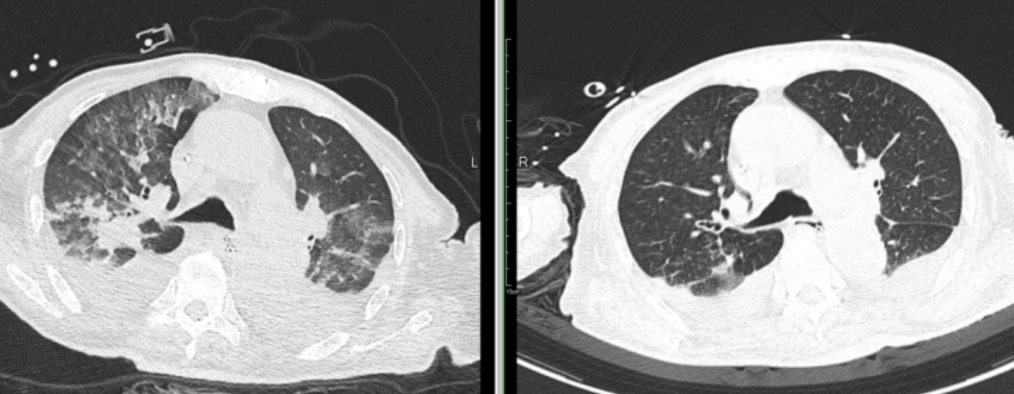

肺部 CT:1. 双肺下叶多发小斑片、索条影较前进展,双肺下叶部分肺组织实变不张,请结合临床;2. 双肺多发实性小结节较前相仿;3. 心包少量积液较前略增多,心包内高致密影,请结合临床;4. 双侧胸膜轻度增厚;5. 动脉硬化;6. 双侧胸腔少量积液,较前略增多;7. 脂肪肝。

图一 患者肺部 CT:左 8 月 4 日,右 8 月 27 日